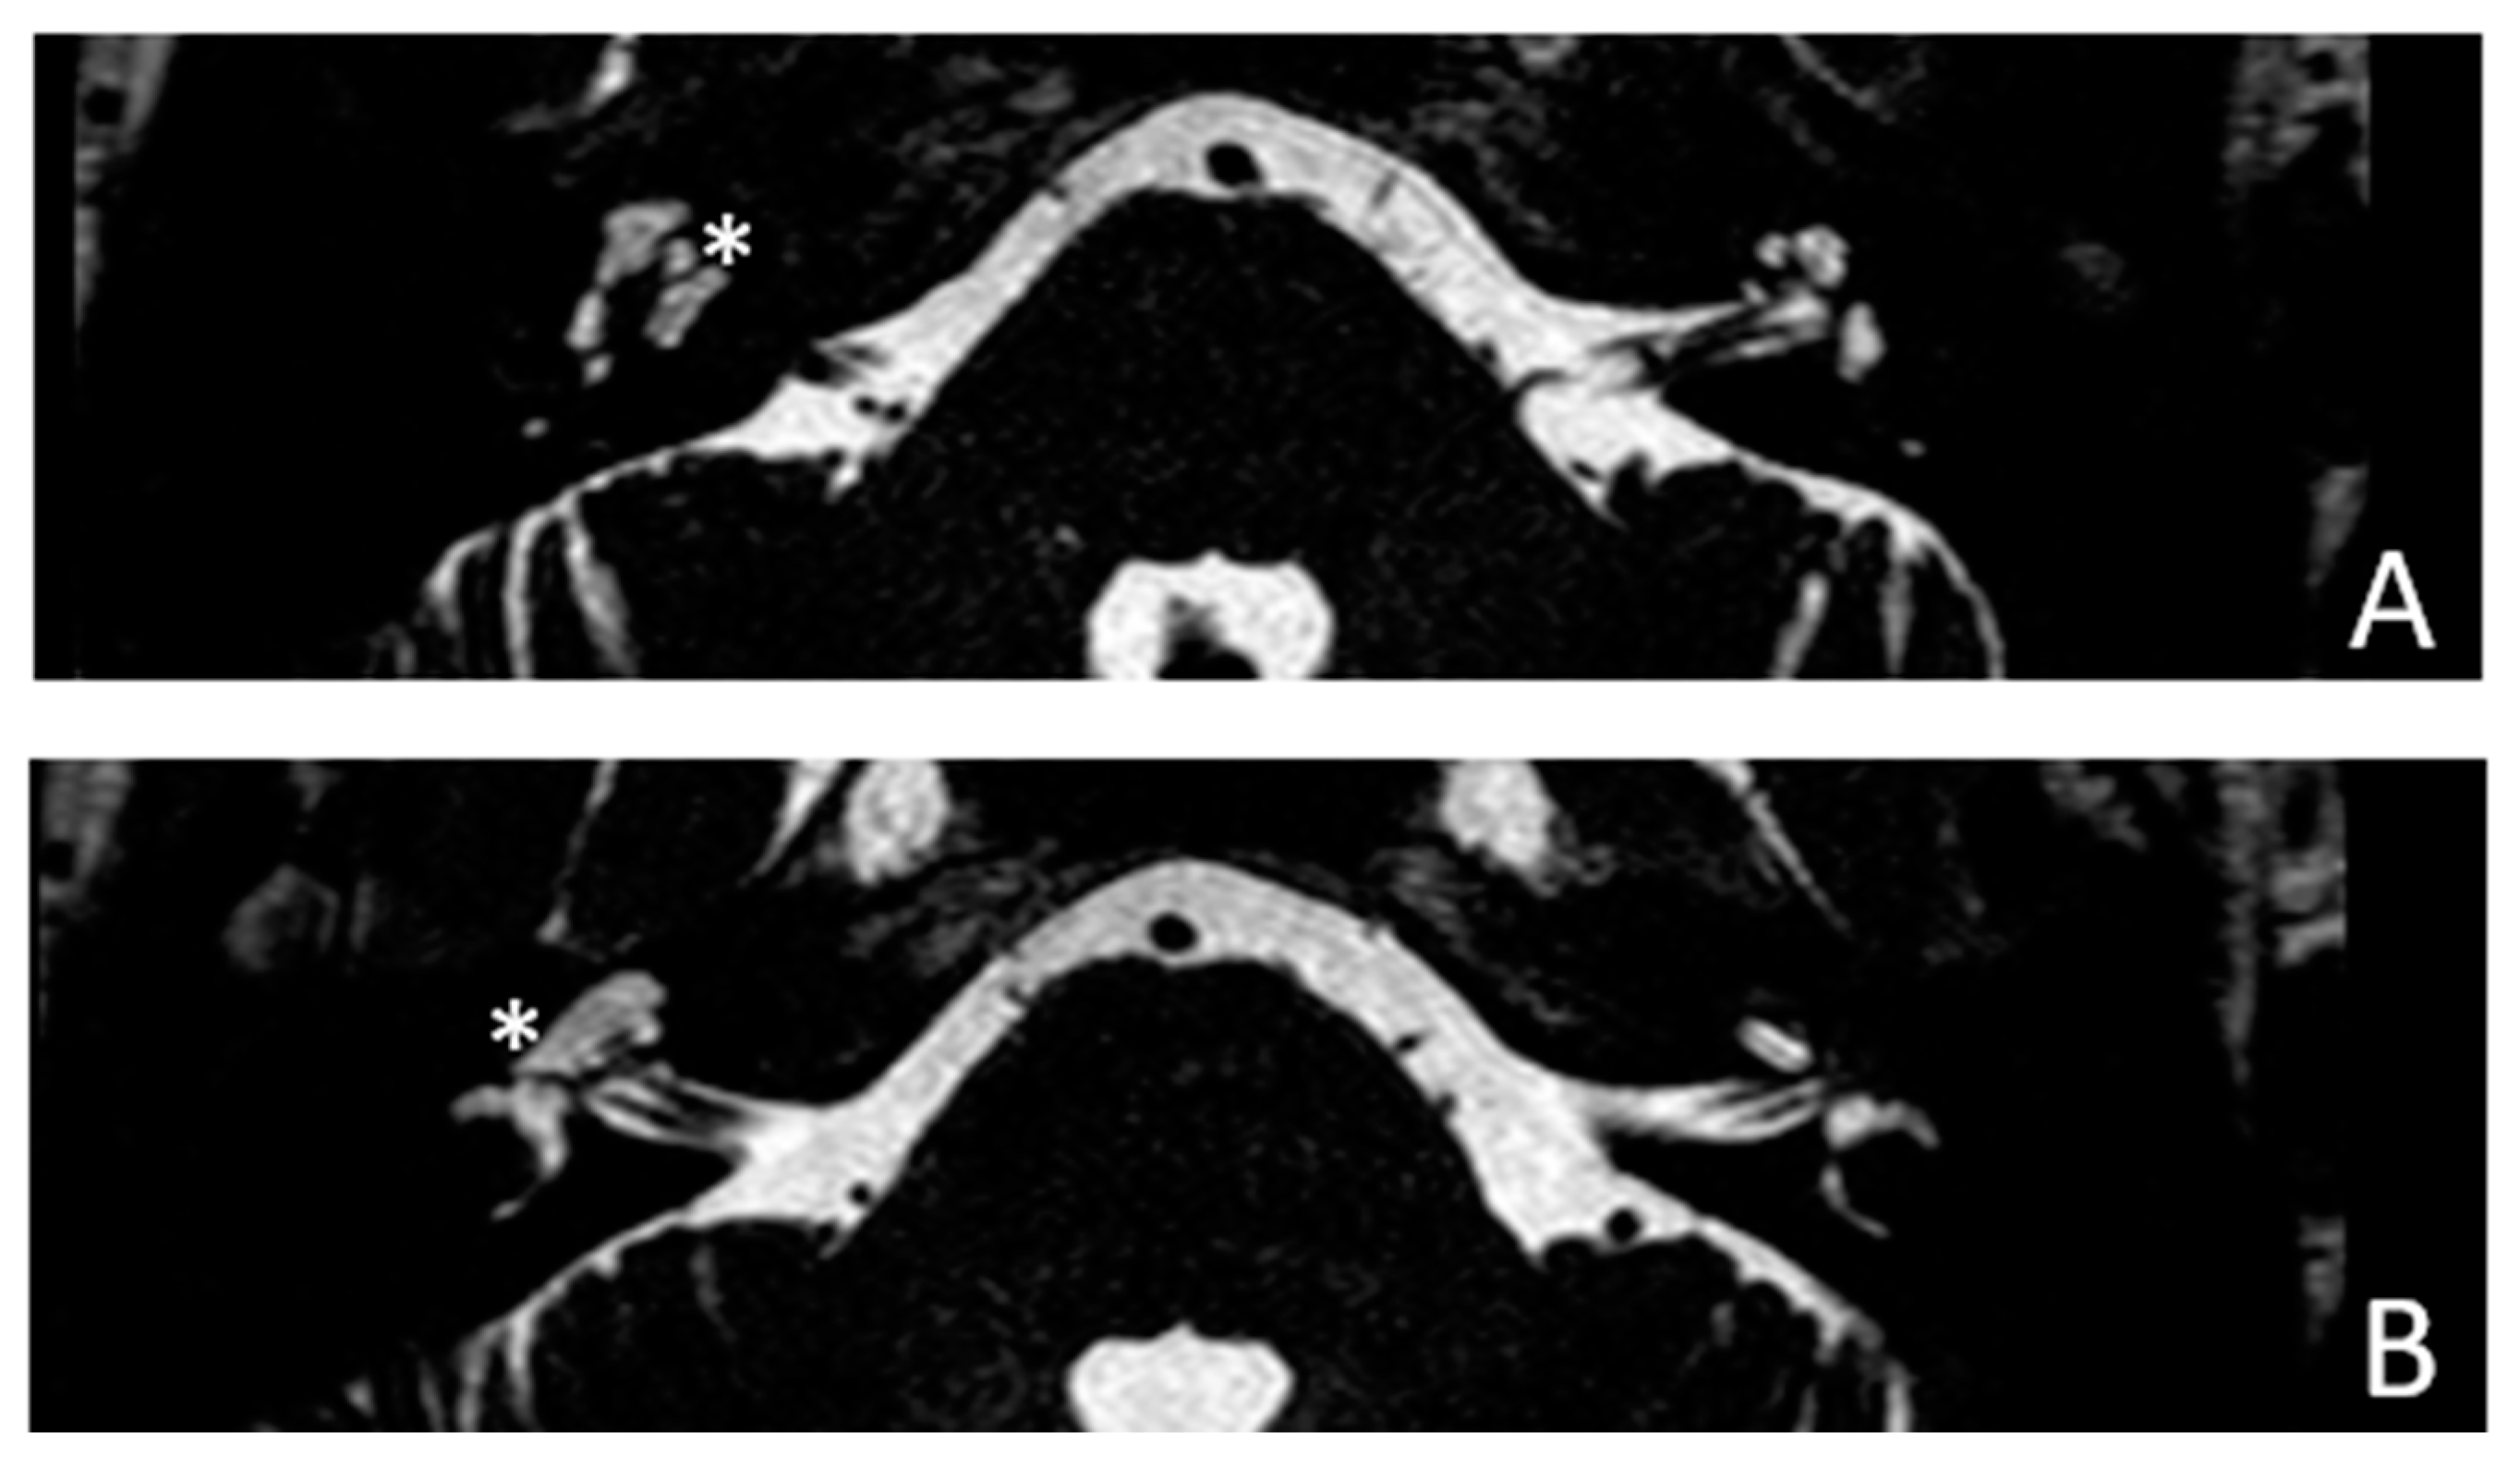

Figure 6. MR images of patient #3 with otosclerosis and SSC dehiscence on the left side. MR cisternography: A and B, axial plane. Note the fluid-signal in the newly formed cavity (white asterisk).